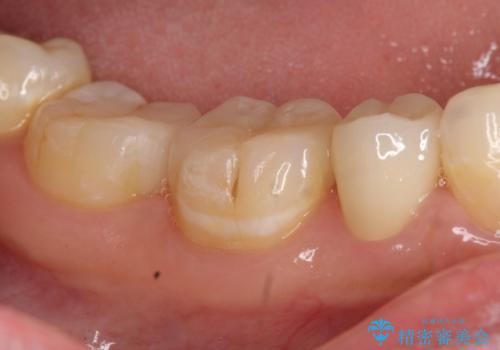

右下5は虫歯が大きかったため、虫歯を除去後、オールセラミッククラウンによる補綴を行いました。

右下6、7は虫歯を除去後、セラミックインレーによる修復を行いました。

当院のセラミックインレーはemaxという強度と審美性に優れた材料を使用しています。

またプレス方式でインレーを製作しているため、削り出しで製作するCADCAMより優れた適合性も持ち合わせており、虫歯が再発しにくい修復物です。

今回用いたオールセラミッククラウンはジルコニアフレームという白い素材の上にセラミックを盛っているため、審美性が非常に高いのが特徴です。

また、ジルコニアは人工ダイヤモンドの材料にも使われているほど高い強度を持っており、そのためオールセラミッククラウンは審美性だけでなく、奥歯やブリッジの補綴も可能とするクラウンです